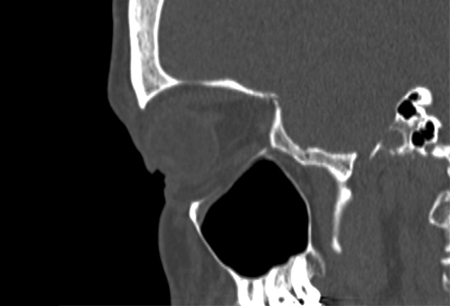

No evidence of fracture on the left orbit as seen on CT-scan; sagittal reconstruction

From the personal collection of Dr Alistair Cobb